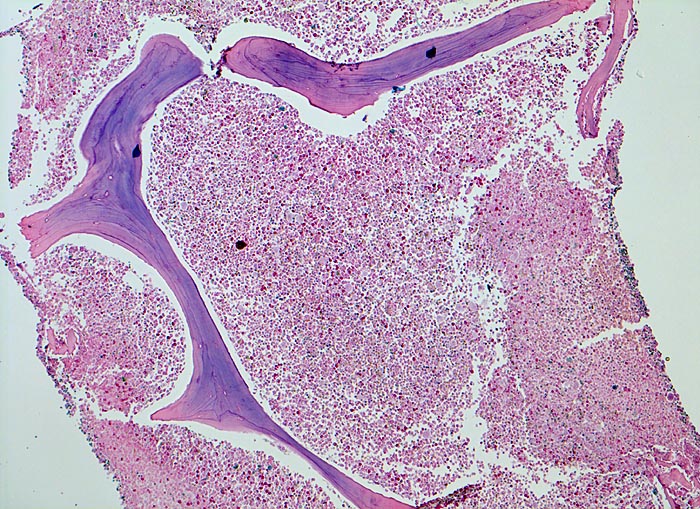

chronische myeloische Leukämie (CML)

Knochenmark, Beckenkamm

Vollständige Verdrängung von normalem blutbildendem Mark und Fettmark durch verschiedene Reifungsstufen der Myelopoese (buntes Bild). Zellularität gegen 100% (sogenanntes "packed marrow").

Müdigkeit und Gewichtsverlust. Ausgeprägte Leukozytose, Basophilie und leichte Anämie. Palpable Milz.

Das Verhältnis weisse zu roten Blutzellvorstufen liegt im normalen Knochenmark des Erwachsenen etwa bei 3:1, kann bei reaktiven Veränderungen aber stark verschoben sein. Die Zellularität ist altersabhängig. Als grobe Faustregel kann man davon ausgehen, dass das Knochenmark bei einem Kind fast 100% blutbildendes Mark enthält. Pro Jahrzehnt wird etwa 10% des blutbildenden Marks in Fettmark umgewandelt. Ein 50 jähriger hat somit ein etwa ausgeglichenes Verhältnis von blutbildendem Mark zu Fettmark.